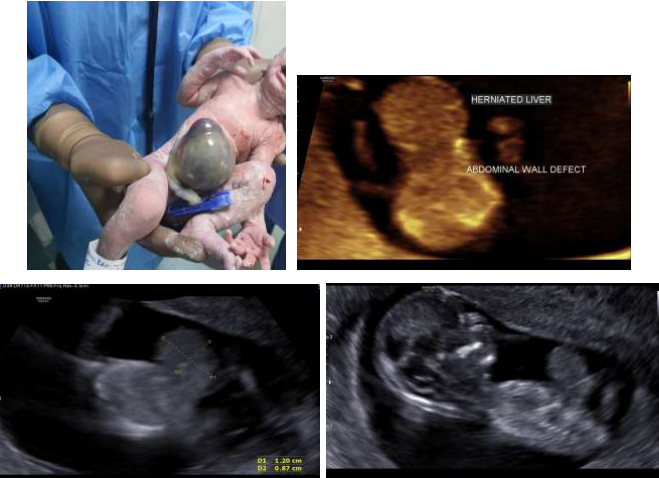

40 yrs old primigravidae conceived by IVF in first attempt reported for routine Antenatal USG examination. There was no family history of any congenital anomaly or any previous spontaneous abortion. Ultrasound of 12 weeks gestation showed defect in anterior abdominal wall in the midline with a mass in the midline protruding through defect. Abdominal wall defect with sac containing liver covered with peritoneum. Herniated sac measures 12 mm x 8.7 mm x 13.6 mm. There is exomphalos. No foetal ascites or polyhydroamnios is seen. No other anomaly seen in fetus.

Figure 1